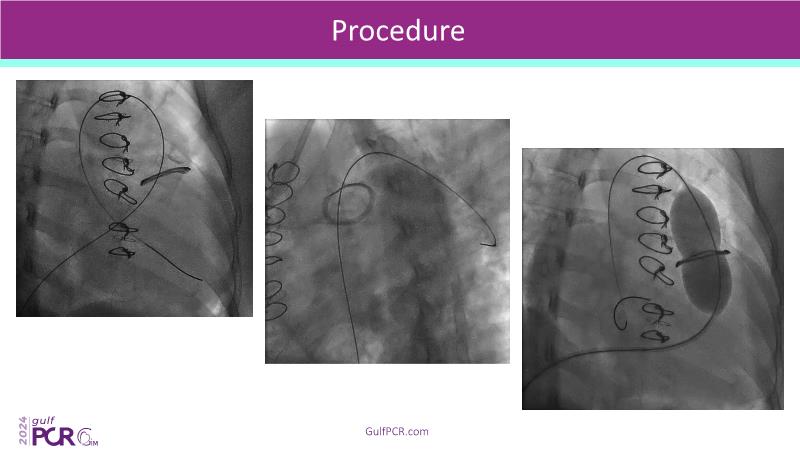

Stay ahead in TAVI innovation by exploring the advanced balloon-expandable Myval THV series. This session highlights the latest clinical data, optimal sizing and implantation techniques, and valuable real-world insights, including long-term follow-up results.

- To understand the best practices for Myval sizing and implantation technique for best outcomes